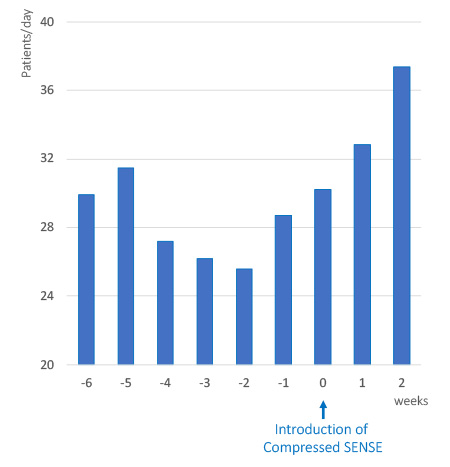

1日あたりの検査数の増加

通常の検査予約枠に新たな検査枠を追加

多くの施設でCompressed SENSEを既存のMR装置に導入し、画質を損なうことなく撮像時間の短縮を実現しています。患者数の多い医療機関では、短縮できた時間を活用し、通常の予約枠に新たに検査枠を追加しています。これにより、検査の予約待ちが減り、患者や検査を依頼した診療科に対し円滑にMR検査を提供できます。

同じスキャン時間で、1日あたりの患者数が増加

ドイツのRadiology and Nuclear Medicine Joint Practice GöttingenのDirk Wagner医学博士、Björn W. Raab医学博士らは、Compressed SENSEを導入したことによって患者1人あたりの検査時間を平均15から11分に短縮することができたと報告しており、1日あたりの検査数を5件増やすことができました。2

患者スループットの増加、MRIタイムスロットの短縮

Compressed SENSEを使用すると、画質を損なうことなく撮像シーケンスを高速化することができます。子安脳神経外科クリニック(KNC)では、検査枠時間の短縮を実現しました。これにより、MR検査のスループットが向上し、1日あたりの検査数が平均 3件増加しました。